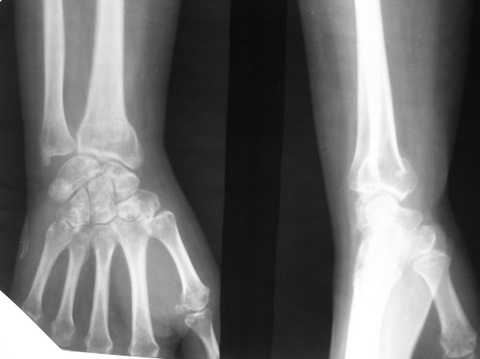

Уважаемые коллеги, обращаюсь к вашему опыту. Обратилась женщина 45лет, профессия - швея, травма 24.02.07 вколоченный перелом правого луча (см Ргр )

на Ргр нарастают явления остеопороза, не смотря на прием препаратов кальция.

Видимо там был оскольчатый перелом луча и шиловидного отростка

локтевой кости.

В гипсовом повязке наблюдалось вторичное смещение костных отломков по длине (при передне-заднем рентгенограмме), и при боковй проекции видно смещение отломка в дорсальном направлении и таким

образом последный дает компрессию нервов в лучезапястном канале (типа синд. Зудека)